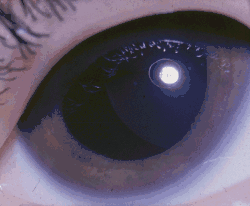

Zespół Weilla-Marchesaniego (ang. Weill-Marchesani syndrome, WMS) – rzadki, uwarunkowany genetycznie zespół wad wrodzonych, na który składają się niskorosłość, brachydaktylia, sztywność stawów i charakterystyczne wady narządu wzroku: mikrosferofakia (zbyt mała soczewka oka ma dodatkowo nieprawidłowy kształt), ektopia soczewki, ciężka krótkowzroczność i jaskra wrodzona. Dziedziczenie jest najczęściej autosomalne recesywne, rzadziej autosomalne dominujące.

- wady soczewki: mikrofakia, afakia, stożek soczewki

- zwichnięcie soczewki

- jaskra wrodzona